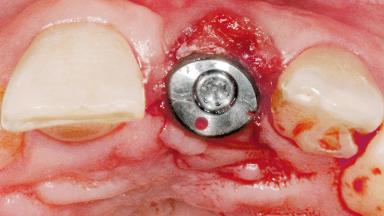

Late Flapless Placement of an Implant in a Maxillary Left Central Incisor Site

Type of Implants One-Piece

Attachment One-Piece

Bone Augmentation Horizontal|Staged

Augmentation Materials Xenogenous|Membrane

Soft Tissue Grafting Simultaneous